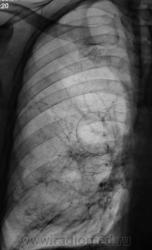

Картинка действительно - ИНТЕРЕСНАЯ...хронический бронхит, пневмофиброзные изменения, больше справа, булллезные изменения справа. И почему то, глядя на в\долю правого легкого, вспоминается о т.н. "тающем легком", хотя это, наверное, и не так....

"Буллезно-эмфизематозная дистрофия легких была описана Burke в 1977 году под названием «исчезающее легкое». Эта патология встречается редко, однако о ней необходимо помнить, так как в ряде случаев прогрессирование дистрофических процессов в легких приводит к образованию и увеличению воздушных полостей за счет исчезновения легочной ткани, что в итоге приводит к пневмотораксу и выраженной легочной, легочно-сердечной недостаточности. К сожалению, из-за образования напряженного клапанного или открытого пневмоторакса ликвидировать последний активной аспирацией содержимого плевральной полости не всегда возможно и значит не удается облегчить состояние больного, а это необходимо, так как воздушные полости в легких сами по себе приводят к дыхательной недостаточности. Единственным способом добиться улучшения состояния больного является торакотомия. Удаление пузырей сохраняет паренхиму легкого от дальнейшего сдавления и разрушения. "

"L. Heilmeyer и A Schmid (1956) описали картину болезни, которая характеризовалась исчезновением легочной ткани, включая бронхи, сосуды в части легкого (сегмент, доля) или во всем легком. Болезнь склонна к прогрессированию. Этиология и патогенез неясны. Заболевание обозначают по-разному: исчезающее легкое, идиопатическая легочная атрофия, буллезная легочная эмфизема.

От обычной картины обструктивнои эмфиземы это заболевание отличается по крайней мере тремя признаками: ограниченностью процесса, который захватывает только часть легких (чаще одну, две доли), а не оба легких полностью, более выраженной потерей тканевой структуры легкого и тенденцией к относительно быстрому прогрессированию заболевания.

Заболевание чаще всего поражает пожилых мужчин, у которых обнаруживаются симптомы бронхита и эмфиземы. Основу процесса составляет субстанциальная эмфизема с образованием крупных булл."

Первый срез.

Второй срез.

Более вероятна бронхо-легочная киста

Для гипоплазии артерия должна быть недоразвитой. А на томограммах нормальных размеров и диаметра артерия огибает некую овальую зону. Все-таки скорее киста, уважаемый Валентин Львович.

Но ведь тех же артерий на единицу площади справа в в\доле ГОРАЗДО меньше....

На мой взгляд, В.Г. прав. Похоже на прогрессирующую легочную дистрофию.

Складывается впечатление об отсутствии межолевых борозд...что наверное косвено может свидетельствовать об аномалии развития..